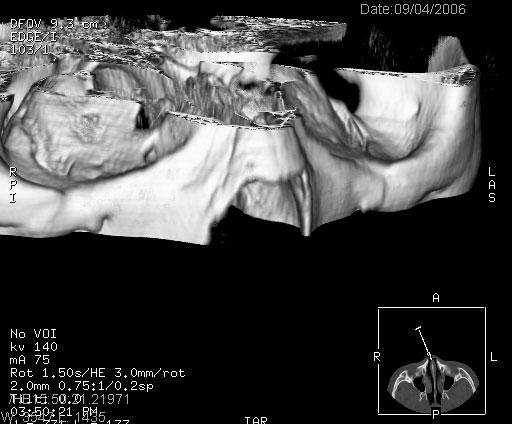

ct:平扫+冠扫:双侧鼻骨对比,冠扫s6#示右侧鼻骨尖部可见线状低密度影,边缘光滑,并见硬化.软组织未见肿胀.

诊断意见:鼻额缝(鼻骨与上颌骨额突缝),但个别同志认为是骨折.因此请同行们会诊.多谢了!